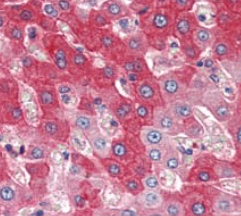

IHC    1/200 - 1/1000